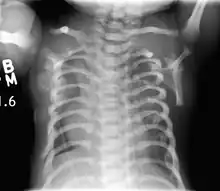

| CXR of a newborn with asphyxiating thoracic dysplasia. Note the short ribs. | |